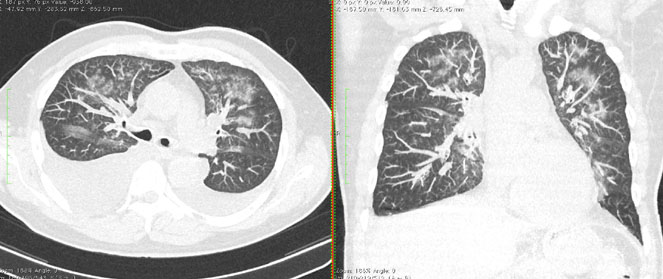

КТ имеет высокую чувствительность в выявлении изменений в легких, характерных для COVID-19. Применение КТ целесообразно для первичной оценки состояния ОГК у пациентов с тяжелыми прогрессирующими формами заболевания, а также для дифференциальной диагностики выявленных изменений и оценки динамики процесса. КТ позволяет выявить характерные изменения в легких у пациентов с COVID-19 еще до появления положительных лабораторных тестов на инфекцию с помощью МАНК. В то же время, КТ выявляет изменения легких у значительного числа пациентов с бессимптомной и легкой формами заболевания, которым не требуется госпитализация. Результаты КТ в этих случаях не влияют на тактику лечения и прогноз заболевания при наличии лабораторного подтверждения COVID-19. Поэтому массовое применение КТ для скрининга асимптомных и легких форм болезни не рекомендуется.

3. Применение лучевых методов у пациентов с симптомами ОРВИ легкой степени тяжести и стабильном состоянии пациента, возможно только по конкретным клиническим показаниям, в том числе при наличии факторов риска, при условии достаточных технических и организационных возможностей. Методом выбора в этом случае является КТ легких по стандартному протоколу без внутривенного контрастирования или РГ при ограниченной доступности КТ. Использование УЗИ в этих случаях нецелесообразно. Применение КТ исследования в сроки ранее 3 - 5 дней с момента появления симптомов заболевания является нецелесообразным.

4. Все выявляемые при лучевых исследованиях признаки, включая КТ-симптомы, не являются специфичными для какого-либо вида инфекции и не позволяют установить этиологический диагноз. Вне клинической (эпидемической) ситуации они не позволяют отнести выявленные изменения к пневмонии COVID-19 и дифференцировать их с другими пневмониями и невоспалительными заболеваниями. Данные лучевого исследования не заменяют результаты обследования на РНК SARS-CoV-2. Отсутствие изменений при КТ не исключают наличие COVID-19 и возможность развития пневмонии после проведения исследования.

5. Рекомендовано проведение лучевого исследования пациентам при среднетяжелом, тяжелом и крайне тяжелом течении ОРИ с целью медицинской сортировки, оценки характера изменений в грудной полости и определения прогноза заболевания:

- выполнение КТ легких без внутривенного контрастирования в стационарных условиях или в амбулаторных - при показаниях к госпитализации;

9. Оценка динамики течения выявленной пневмонии COVID-19 проводится по клиническим показаниям с применением следующих методов визуализации:

- оптимально: выполнение КТ исследования легких по стандартному протоколу без внутривенного контрастирования;